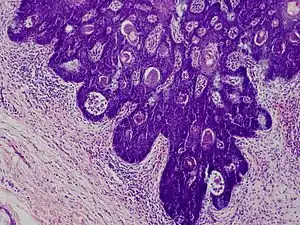

Folliculosebaceous cystic hamartoma

Folliculosebaceous cystic hamartoma abbreviated as (FSCH) is a rare cutaneous hamartoma consisting of dilated folliculosebaceous units invested in mesenchymal elements.[1]:676 it typically affects adults, have a predilection for the central face or scalp, with less than 1.5 cm dimension.[2] Clinically, the lesions are asymptomatic, rubbery to firm in consistency, and usually occur on or above the neck in (> 90%) of cases, Histopathologically, FSCH shares several similar features to sebaceous trichofolliculoma, but it is usually possible to differentiate these two tumors.[3]